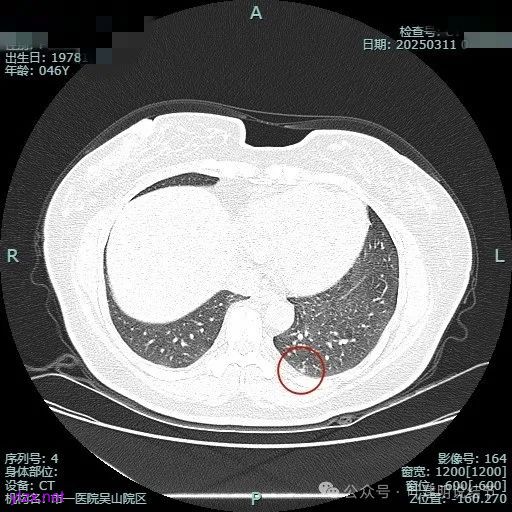

时间很快到了2025年3月,结友又来我门诊复查,我还以为她在别处开了刀了呢,结果并没有,说是与家人商量后决定吃中药三个月看看能不能好。我们来看看再复查的情况,中药有没有起作用:

总体感觉三处病灶边缘的淡磨玻璃成分好转不太明显了,实性成分较前略显致密点,大小与形态是说不上显著变化的。所以有几点可以肯定:1、消炎没有效;2、中药没有用;3、考虑多原发肺癌,且为浸润性腺癌可能性大些,得手术!

左下叶基底段微小结节,也是混合密度偏实性,瘤肺边界稍不清,与右侧的是类似形态的。

病灶3:

病灶混合密度,但瘤肺边界不够清楚,灶内也不太致密。

整个显得有点模糊,虽有血管进入,但血管说不上显著异常增粗,病灶边缘有细毛刺,贴胸膜近,但缺乏明显收缩力。

病灶显糊,轮廓较清但瘤肺边界欠清晰。

有血管进入,但病灶的感觉总好像缺乏收缩力,也聚拢性不太够。